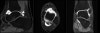

발목의 MRI 관절조영술

Arthrogram sequences of the ankle evaluate the talar cartilage and allow for staging of ostechondral defects of the talar dome.

They can also better evaluate the joint capsule and its boundaries such as the anterior talofibular ligament.